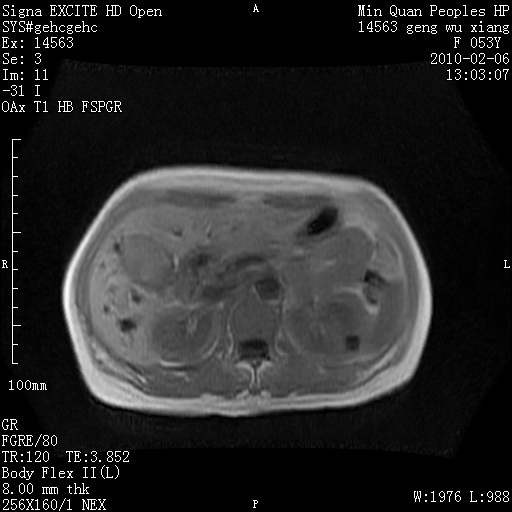

标题: MRI2762:胆道梗阻原因?

f,53y,全身黄染多日。

高位胆道梗阻 胆管癌可能性大

支持 高位胆道梗阻 胆管癌可能性大。